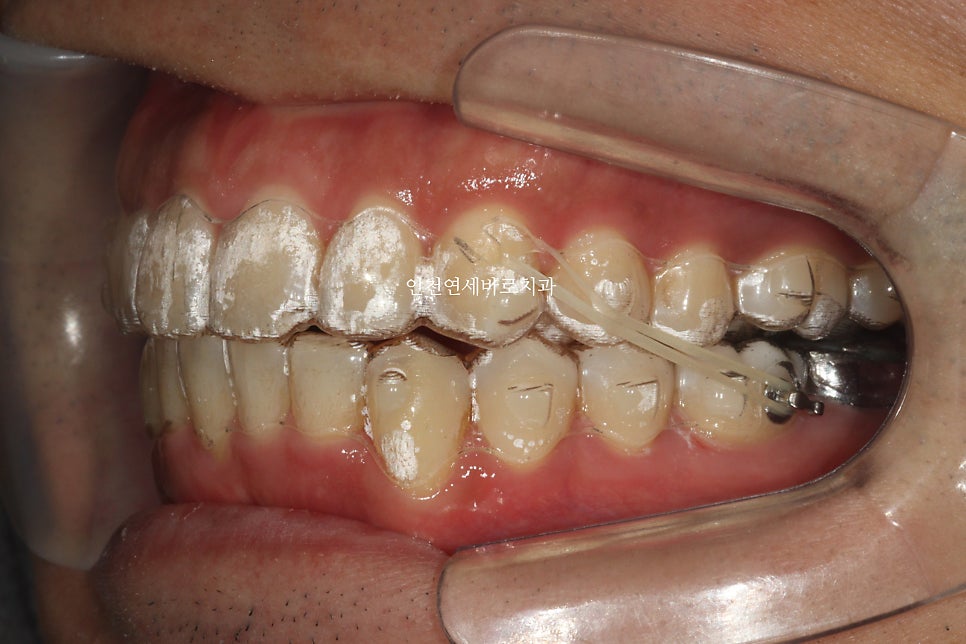

약 1달의 제작기간이 소요된 후 2023.5.17에 치료를 시작하셨습니다.

한번의 재제작을 시행하였습니다.

치료 전과 후의 비교입니다.

1회의 재제작.

각 제작마다 1달의 시간 소요

실질 치료기간 약 1년입니다.